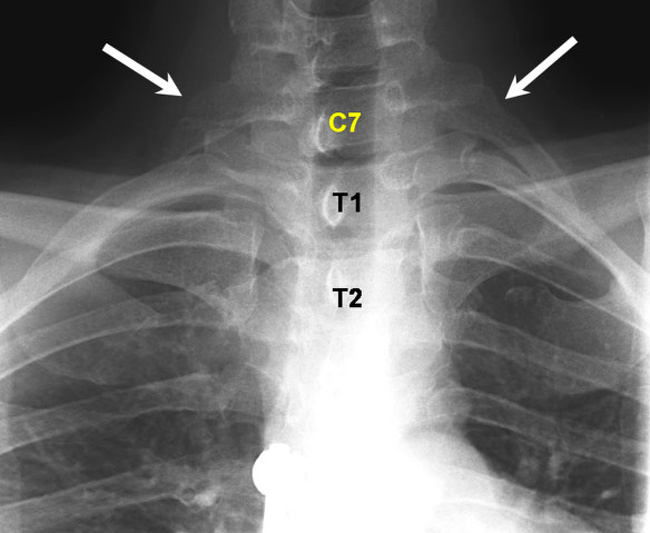

▼9.多出來的肋骨:這種特徵在女性身上比較常見。多出來的肋骨往往在頸椎部位,尺寸有大有小。在一般情況下,這對健康沒什麼影響,只是偶爾覺得不太舒服。